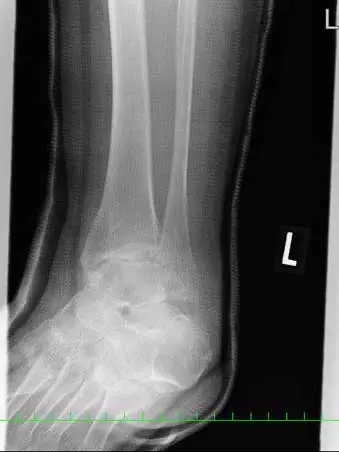

(図5)術後X線像

脛骨内果はcancellus screw2本、腓骨外果は1/3円プレート、脛骨天蓋部は骨欠損部にオスフェリオンを充填し、cancellus screw2本にて固定している。踵骨裂離骨片はスパイクワッシャー付cancellus screwにて固定し、Leeds-Keio人工靭帯にて補強している。